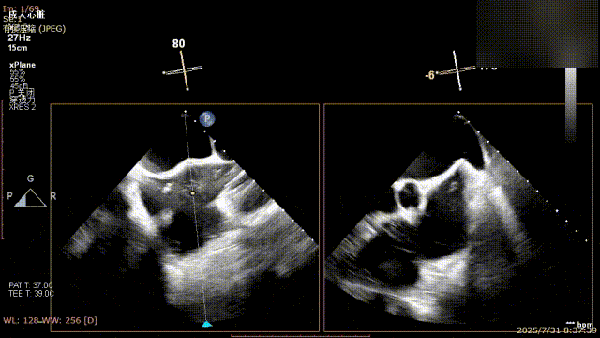

术前完善经食管超声评估,提示该患者双房大,二尖瓣重度反流4+伴后叶脱垂、后叶部分腱索断裂。根据评估结果,心脏大血管外科王安彪主任团队制定了周密的手术方案:植入一枚夹合器,钳夹P1区反流最大处,尽可能夹持全部后叶脱垂瓣叶组织,后续根据术中实时残余分流和跨瓣压差等指标,并依据实时超声监测调整治疗策略。

三维评估;二尖瓣P1脱垂偏心性返流

术前影像